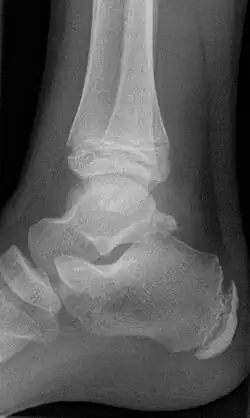

Beim Röntgen ist das Os trigonum als dreieckiges, rundes oder ovales Gebilde am Processus posterior tali bei seitlicher Aufnahme am besten zu erkennen. In den meisten Fällen ist es ein einzelner Knochen, es können aber auch mehrere Os trigonum ausgebildet sein.